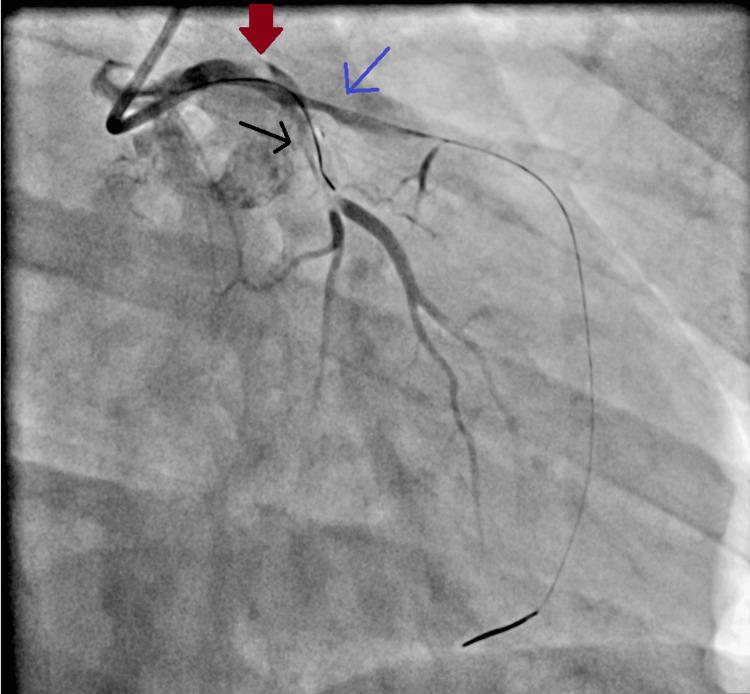

静脉-动脉体外膜肺氧合(vaECMO)撤机后发热的意外原因:一例报告

Fever following decannulation from extracorporeal membrane oxygenation (ECMO) poses diagnostic challenges. While infectious causes and thrombosis are typically considered, rare etiologies may be overlooked. We report the case of a 47-year-old woman who developed a high, refractory fever following veno-arterial (va) extracorporeal membrane oxygenation decannulation. Extensive infectious and non-infectious workups failed to identify a definitive cause as cultures, imaging modalities, and inflammatory markers were inconclusive. On post-ECMO day 9 and 23 days after initial admission to the hospital, a gynecological examination was prompted by unexplained unilateral labial edema and prolonged menstruation. Speculum examination revealed a retained menstrual cup embedded in the cervix, causing local inflammation. Following its removal, the patient's fever rapidly resolved, without the need for further antibiotic escalation. Menstrual cups are generally considered safe, with rare complications such as toxic shock syndrome, pelvic infections, and mechanical injuries. However, in critically ill patients unable to provide a complete history, retained menstrual cups can lead to significant inflammatory responses and diagnostic delays. This case highlights the importance of maintaining a broad differential diagnosis, including gynecological evaluation, in cases of unexplained fever, particularly in critically ill patients.

体外膜肺氧合(ECMO)撤机后发热带来了诊断挑战。虽然通常会考虑感染性病因和血栓形成,但罕见病因可能会被忽视。我们报告了一例47岁女性,她在静脉-动脉(va)体外膜肺氧合撤机后出现了高热且难治性发热。广泛的感染性和非感染性检查未能确定明确病因,因为培养结果、影像学检查和炎症标志物均无定论。在ECMO撤机后第9天以及入院后23天,因不明原因的单侧阴唇水肿和月经延长而进行了妇科检查。窥器检查发现一个月经杯嵌顿在宫颈内,引起局部炎症。取出月经杯后,患者的发热迅速消退,无需进一步升级抗生素治疗。月经杯通常被认为是安全的,罕见并发症如中毒性休克综合征、盆腔感染和机械性损伤。然而,在无法提供完整病史的重症患者中,月经杯嵌顿可导致显著的炎症反应和诊断延迟。该病例强调了在不明原因发热病例中,尤其是重症患者,保持广泛鉴别诊断的重要性,包括妇科评估。